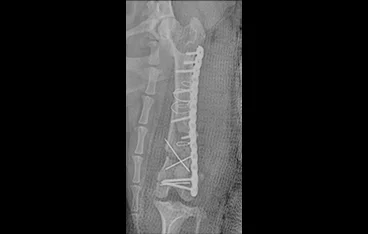

• PLATE

• PLATE 수술 전

PLATE 수술 후